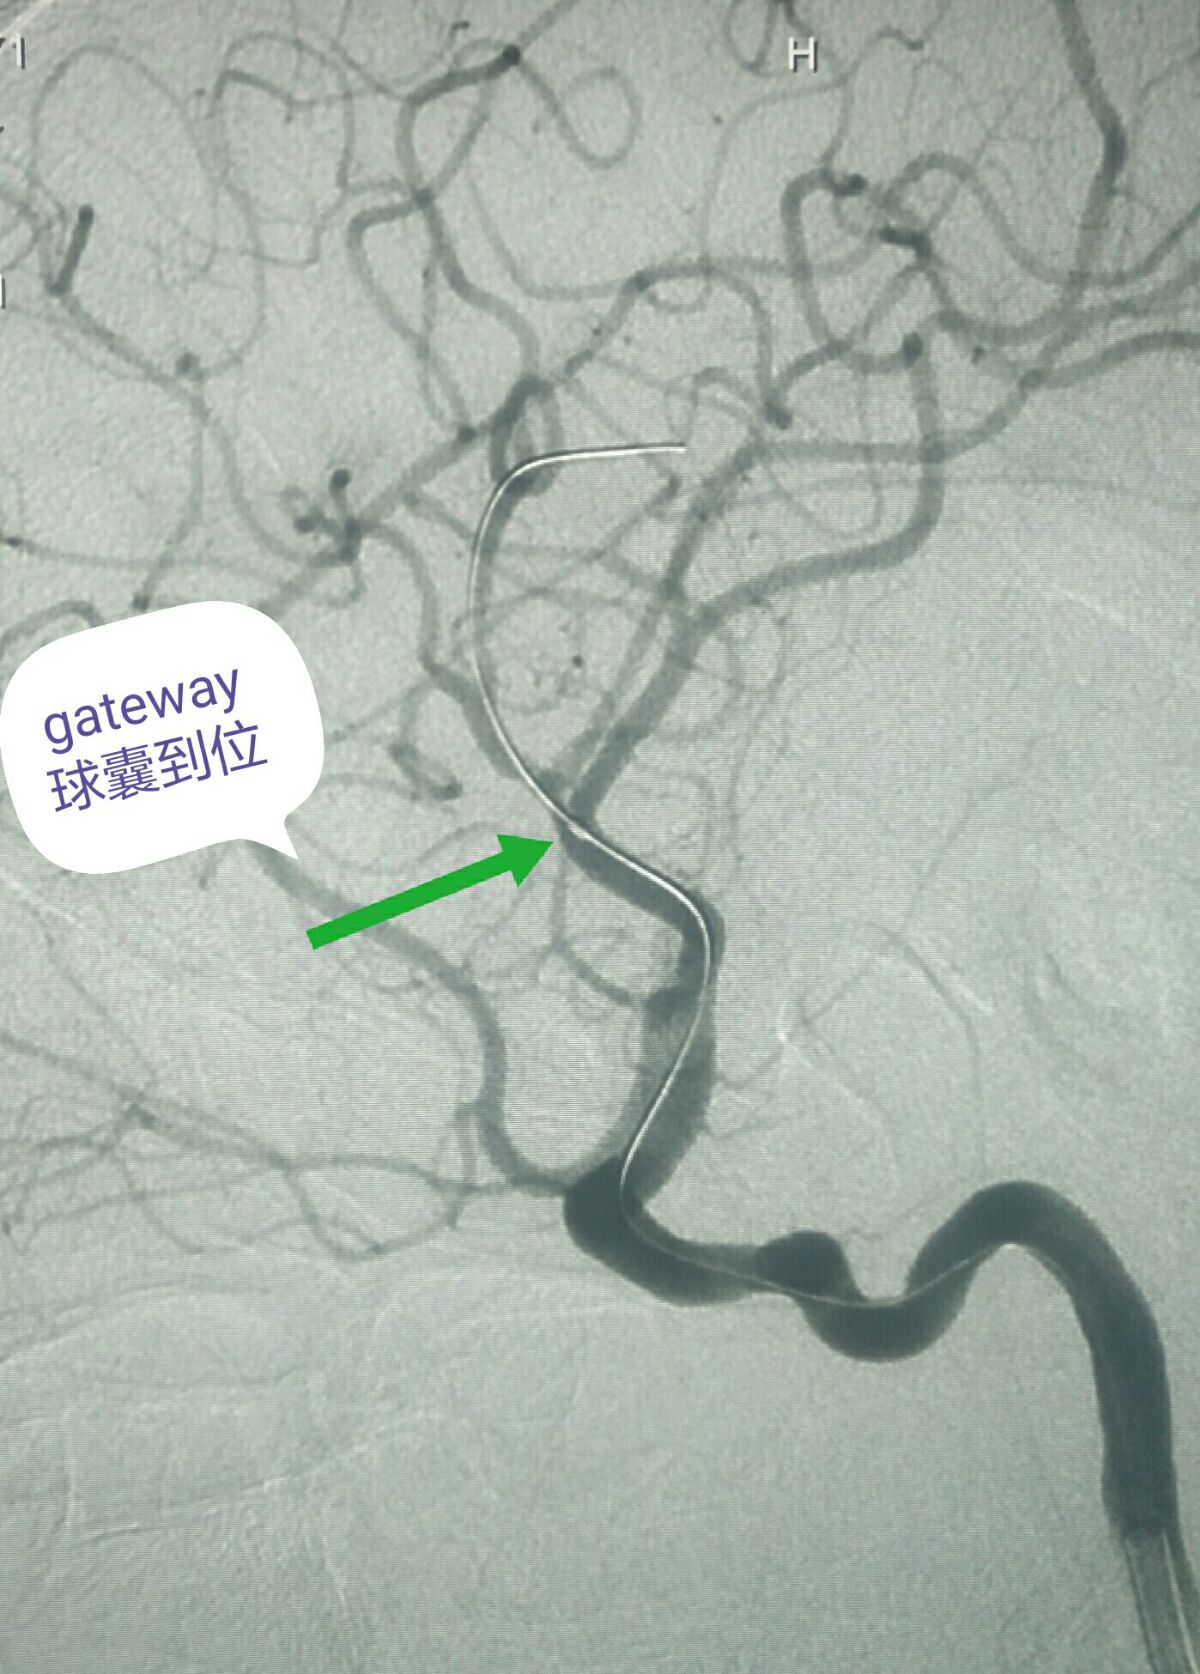

用3米微导丝同轴交换1.5*15的gateway球囊到位